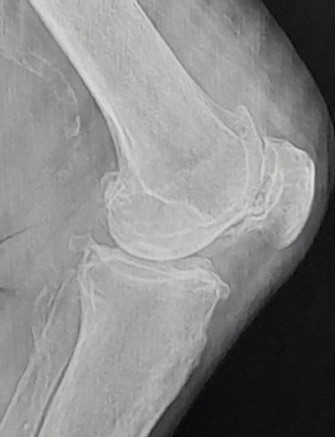

Radiograficamente i segni caratteristici sono:

- Riduzione dello spazio articolare che può colpire uno o entrambi i compartimenti(artrosi monocompartimentale mediale o laterale) causato dalla degenerazione cartilaginea.

- Speroni ossei definiti Osteofiti.

- Cavità di osso degenerato dette geodi.